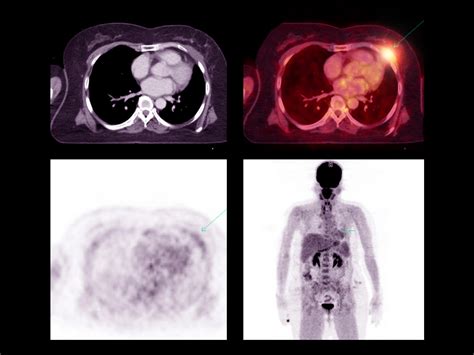

PET-CT scans involve the injection of a radioactive tracer, typically a form of glucose, into the patient's bloodstream. Cancer cells, which have a higher metabolic rate, absorb more of the tracer than normal cells. The PET scanner then detects the radiation emitted by the tracer, creating images that highlight areas of high metabolic activity. Simultaneously, the CT scanner takes detailed images of the body's structures, which are then fused with the PET images to provide a precise location of the cancerous cells.

• Accurate Staging: The detailed images provided by PET-CT scans help in accurately staging the cancer, which is crucial for determining the appropriate treatment plan. Staging involves assessing the size and extent of the tumor, as well as whether it has spread to other parts of the body.

Interpreting the results of a PET-CT scan involves a detailed analysis by a radiologist. The images are reviewed to identify areas of high metabolic activity, which may indicate the presence of cancer. The results are then shared with the patient's healthcare team, who will discuss the findings and develop a treatment plan. It is important to note that while PET-CT scans are highly accurate, they are not foolproof. False positives and false negatives can occur, and additional tests may be needed to confirm the diagnosis.